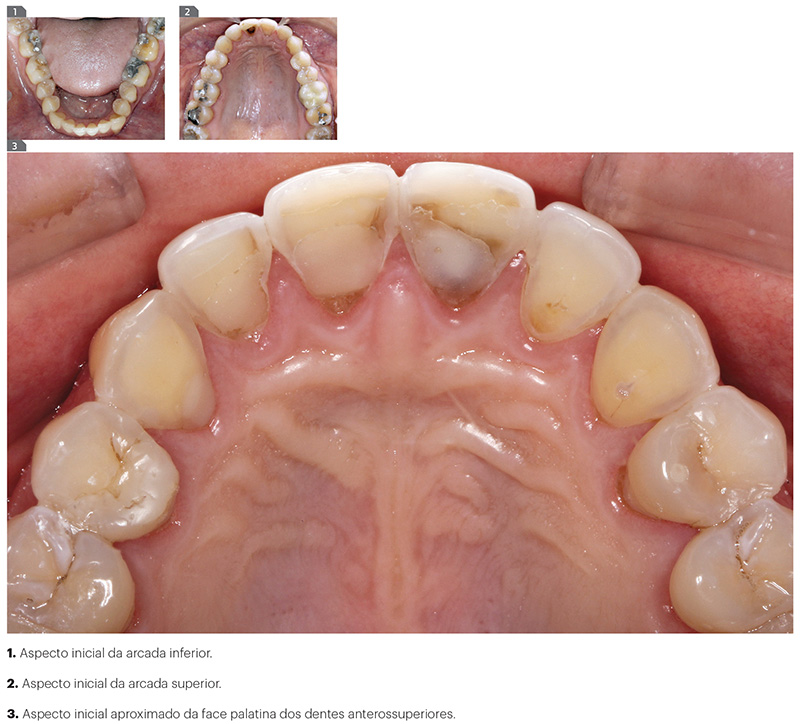

Entretanto, no exame físico intrabucal foram observadas áreas relativas à abfrações cervicais vestibulares, sinais clínicos de bruxismo nos dentes posteriores com facetas de desgaste oclusais, lesões de cáries interproximais e restaurações de amálgama com margens elevadas com sinais de corrosão. A presença de sinais clínicos de erosão ácida foi detectada nas faces palatinas dos incisivos e caninos superiores, com extensa perda de esmalte palatino e margens incisais translúcidas nos incisivos centrais, comprometendo a eficiência oclusal das guias anteriores em protrusão e lateralidade. A região cervical palatina dos pré-molares também apresentava sinais de erosão ácida. Esses achados clínicos não estavam presentes na arcada inferior, que apresentava-se mais preservada.

Diante dessas manifestações bucais, suspeitou-se da ocorrência de distúrbio alimentar. A anamnese da paciente foi retomada direcionando as perguntas de forma mais detalhada, com a finalidade de esclarecer a origem dos sinais clínicos descritos anteriormente. Nesse momento, o enfoque acolhedor das perguntas e a atitude destituída de julgamentos do cirurgião-dentista foi importante e motivou a paciente a relatar espontaneamente a ocorrência de bulimia durante vários anos. O diagnóstico de erosão ácida endógena foi confirmado. A paciente relatou estar sob acompanhamento médico e ter conseguido controlar o problema, o que a motivou a procurar tratamento odontológico (Fig. 1, 2, 3).